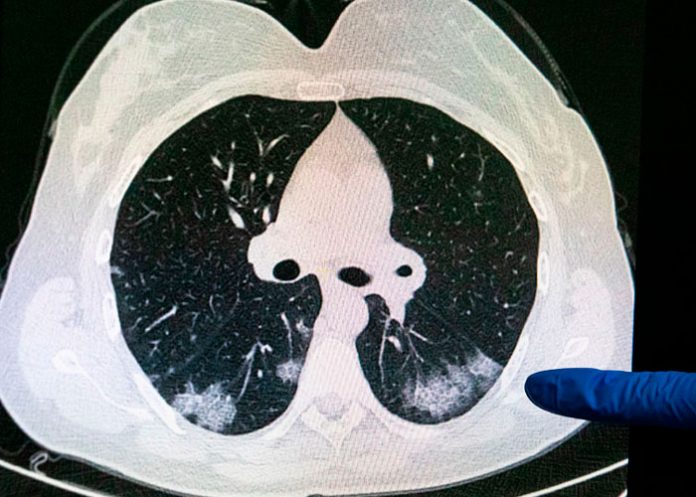

Inicialmente se creía que se trataba de una enfermedad priónica humana, en la que las proteínas llamadas priones provocaban que las proteínas normales se doblaran de forma anormal, pero las pruebas han descartado esa hipótesis